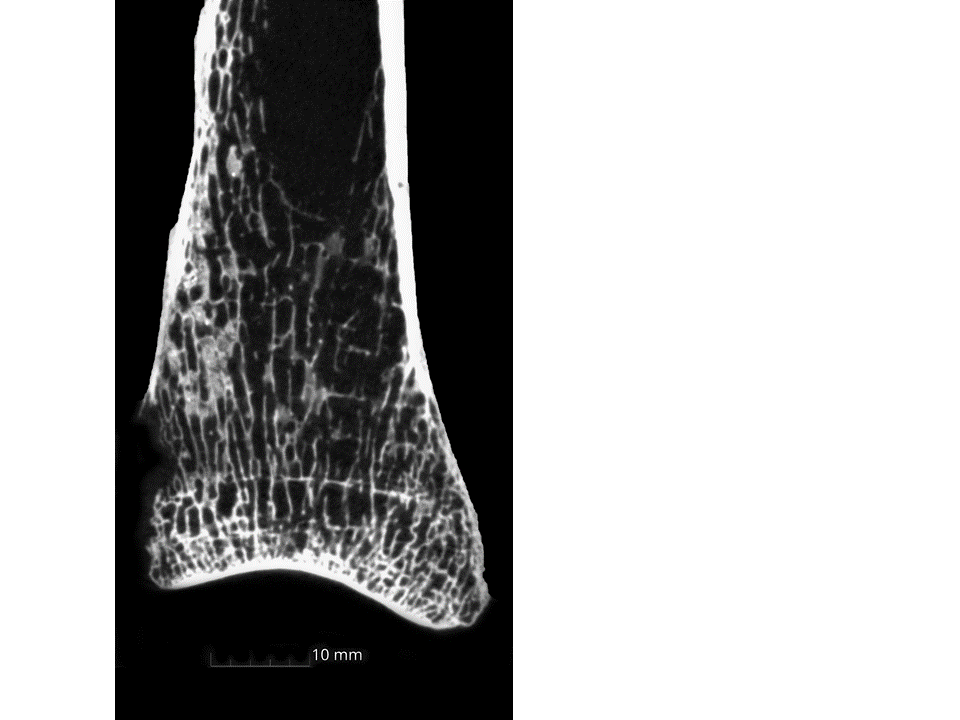

ハリス線の出現頻度は農民の中でも庄屋に属する人々が低く、箱崎遺跡の人々が最も高かった(表)。箱崎遺跡については副葬品の考古学的分析を行った結果、柄鏡や錫杖などといった特殊な副葬品も確認することができ、当該遺跡に埋葬された人々は、他の墓地遺跡と比較して特異な職能を持つ個体が存在したことが明らかになった。しかし、栄養状態は大野城市内遺跡と比較すると悪く、一般農民層よりも生活状態は良くないことが推測された。古人骨の調査によって同じ非都市部の百姓内にもハリス線の出現頻度に差が生じており、このことから階層社会の進展とともに百姓層も階層分化がすすみ、上位層化した一部農民を除く大多数の農民層の貧窮化の影響を表している可能性を明らかにした。

ハリス線の観察によって得られた格差をさらに検討するため、筑紫野市原田遺跡など今回の研究計画に含めていなかった福岡県内の江戸時代遺跡出土人骨のCTによる観察を行う。また、栄養・健康状態の差は食べていたものに起因する可能性が高く、歯石を用いた腔内細菌叢の研究を共同研究として進めている。

ハリス線(横に伸びるライン)